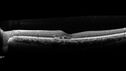

Occult Choroidal Neovascular Membrane

66 year old man with vision loss in the left eye for 2 months

VA 20/20 OD, 20/63 OS